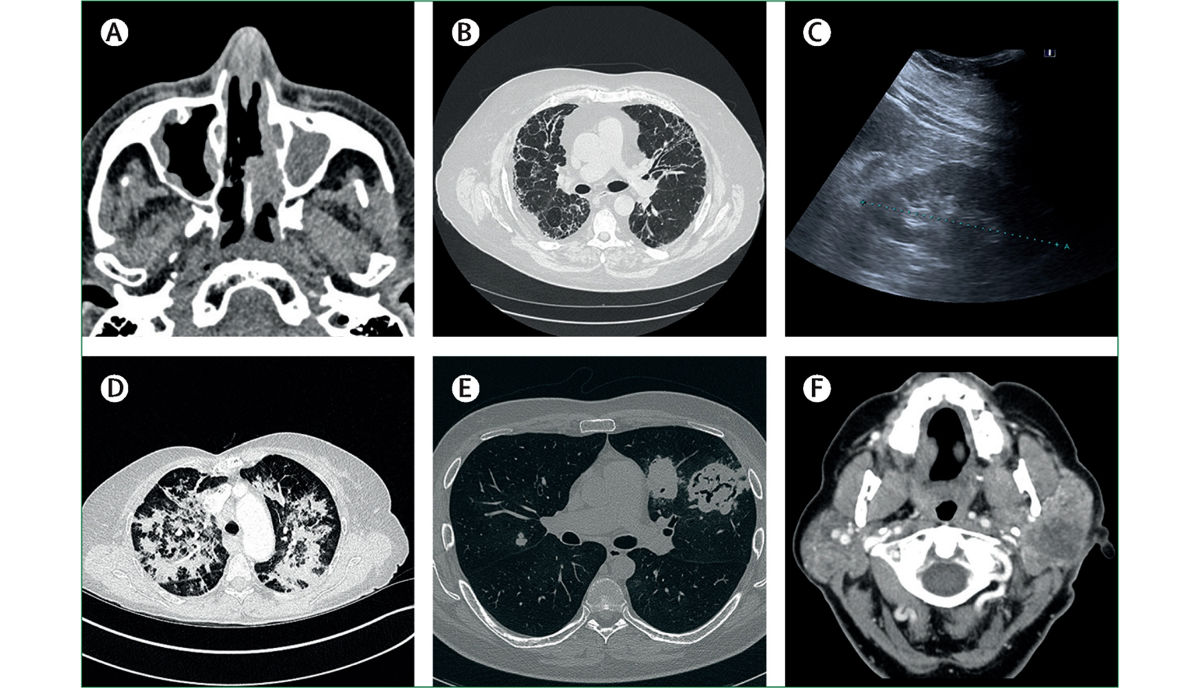

BU: In der Bildgebung zeigen sich Manifestationen von ANCA-assoziierter Vaskulitis

Das diagnostische “State of the art”-Prozedere sieht, wie im Paper beschrieben, zunächst die Erhebung von Blutlabor, allen voran des CRP-Werts und der Blutsenkungsgeschwindigkeit, vor. „Eine Senkung von ≥ 50 Milliliter pro Stunde spricht oftmals für eine systemische Autoimmunerkrankung“, erklärt Kronbichler. In der Folge werden andere Untersuchungen (z.B. CT und MRT, je nach Organbefall) angeordnet. „Das Wesentliche um eine Vaskulitis endgültig zu diagnostizieren, ist aber die Biopsie des symptomatischen Organs“, sagt er. Häufig würden dabei Granulome, also kugelförmige Ansammlungen von Entzündungszellen, oder vaskulitische Manifestationen (v.a der Niere) entdeckt. Anhand der Gewebeprobe können zudem Faktoren für die Prognose bestimmt werden.